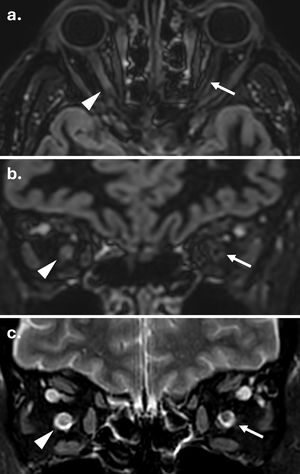

Según los criterios de 2024, la afectación del nervio óptico debe evaluarse principalmente mediante RM, utilizando la tomografía de coherencia óptica y los potenciales evocados visuales como modalidades alternativas11. Cuando se sospecha neuritis óptica aguda, el protocolo de RM recomendado incluye secuencias coronales STIR o T2 con supresión de grasa, e imágenes poscontraste potenciadas T1. Además, las secuencias de doble inversión-recuperación tridimensionales (3D-DIR) pueden mejorar la detección tanto de lesiones sintomáticas como asintomáticas12 (fig. 1).

Detección de lesión del nervio óptico en una persona con esclerosis múltiple mediante secuencias 3D de doble inversión-recuperación (DIR) y T2 con saturación grasa. (a) Reconstrucciones axial y (b) coronal de una adquisición 3D-DIR que demuestran una lesión hiperintensa en el segmento canalicular del nervio óptico izquierdo (flechas). El nervio óptico derecho normal se muestra para comparación (puntas de flecha). (c) Adquisición T2 con saturación grasa al mismo nivel confirma la lesión (flecha) y muestra el nervio óptico contralateral normal (punta de flecha).

Es importante destacar que los hallazgos de la RM ayudan a diferenciar la EM de otras neuropatías ópticas inflamatorias. Las lesiones relacionadas con la EM suelen ser cortas y localizadas anteriormente. La enfermedad asociada a anticuerpos contra la glicoproteína de mielina de oligodendrocitos (MOGAD) se presenta característicamente con lesiones bilaterales longitudinalmente extensas, a menudo simultáneas, con inflamación anterior del nervio óptico y perineuritis, mientras que el trastorno del espectro de la neuromielitis óptica positiva para acuaporina-4 (NMOSD AQP4+) afecta con mayor frecuencia al nervio óptico posterior y al quiasma13.

Diversos desafíos técnicos limitan la imagen del nervio óptico, incluyendo artefactos de movimiento, desplazamiento químico en la interfaz de la grasa orbitaria y efectos de susceptibilidad cerca de los senos paranasales14. La reproducibilidad varía sustancialmente con la optimización de la secuencia y la experiencia del lector15,16. Además, la imagen del nervio óptico ofrece un escaso valor diagnóstico añadido en pacientes asintomáticos, ya que aquellos con lesiones detectables suelen cumplir los criterios DIS a través de la afectación de otras localizaciones anatómicas17. En consecuencia, el consenso MAGNIMS-CMSC-NAIMS de 2024 considera la RM del nervio óptico opcional en casos sin neuritis óptica8.